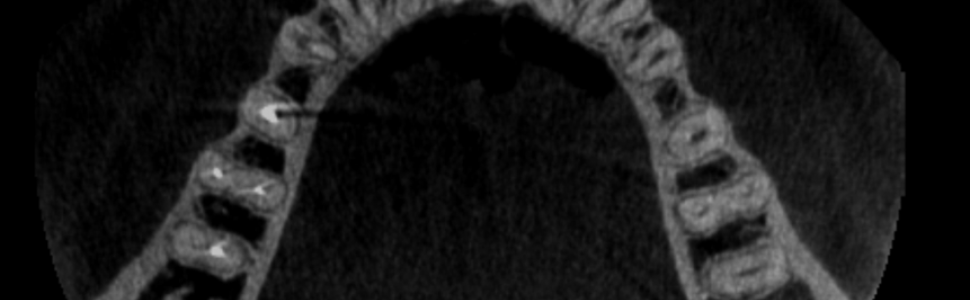

Częstą anomalią morfologiczną systemu kanałowego obserwowaną w drugim zębie trzonowym żuchwy jest tzw. kanał typu C zwany też kanałem C-kształtnym (1-3). Kanał ten swoją nazwę zawdzięcza ułożeniu ujść kanałowych, które w dnie komory tworzą literę C, zwróconą wypukłością w stronę policzkową lub językową (1-3). Kanały typu C występują również, ale znacznie rzadziej, w pozostałych zębach trzonowych (zarówno szczęki, jak i żuchwy), zębach przedtrzonowych dolnych, a bardzo sporadycznie w zębach siecznych bocznych szczęki (1-3). U ludności rasy kaukaskiej, a więc prawdopodobnie również w populacji polskiej, kanał typu C występuje stosunkowo rzadko (poniżej 10% w przypadku drugich zębów trzonowych żuchwy); natomiast u ludności pochodzenia azjatyckiego (Chińczycy, Koreańczycy) występowanie kanałów typu C jest dość powszechne (30-50% drugich zębów trzonowych posiada taką konfigurację kanałów) (4-8). Rozpoznanie, co zazwyczaj nastręcza spore trudności, ustala się na podstawie badania klinicznego i radiologicznego (ryc. 6-8). Istnieje wiele cech klinicznych i radiologicznych wskazujących na obecność kanałów typu C; ich omówienie przekracza jednak ramy niniejszego opracowania.

Ryc. 6. Badanie tomograficzne (CBCT) ukazujące przekrój poprzeczny żuchwy. Widoczny drugi ząb trzonowy prawy z kanałem typu C (jeden korzeń z wklęsłością skierowaną językowo, strzałka niebieska) oraz drugi ząb trzonowy o typowej budowie (korzeń bliższy z dwoma kanałami – strzałka żółta; korzeń dalszy z jednym kanałem – strzałka zielona).